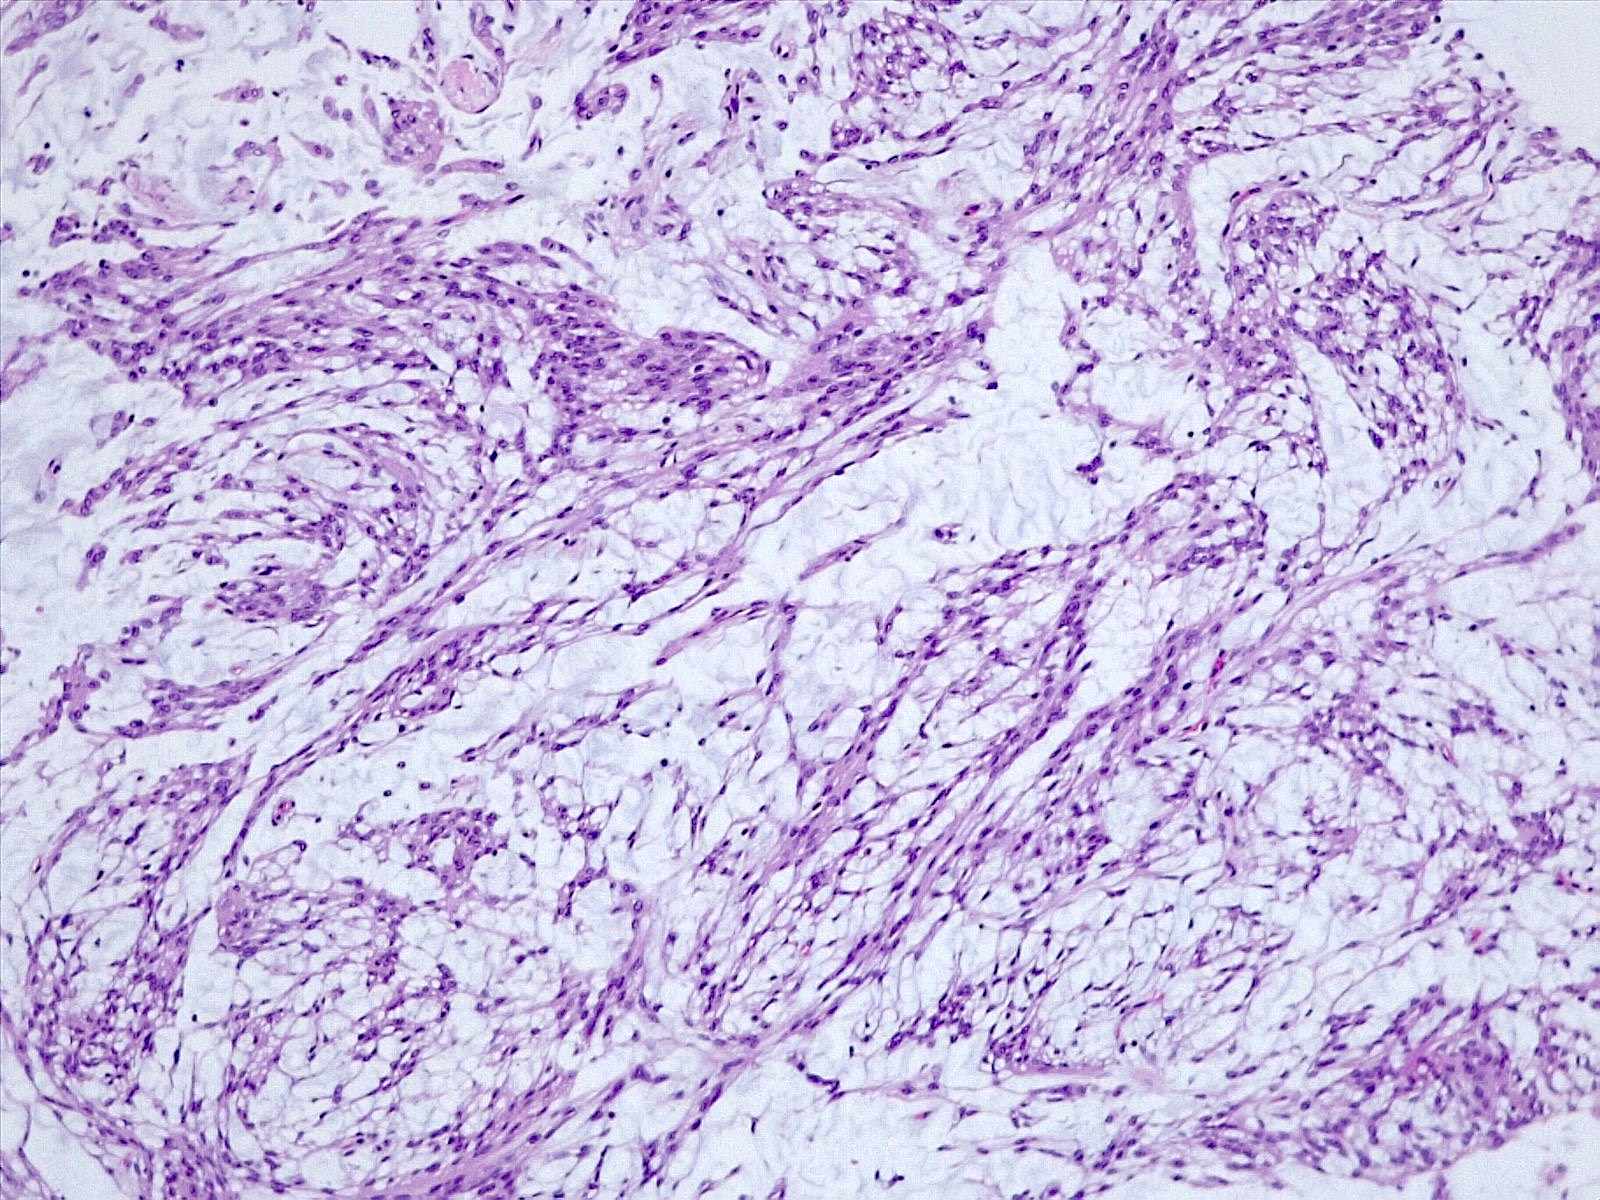

Microscopic (histologic) description

- Histologically reminiscent of chordoma, consisting of epithelioid cells or spindle cells (often partly vacuolated) that are arranged in cords within a pale basophilic myxoid matrix (Am J Surg Pathol 2000;24:899, J Neurooncol 2010;100:465, Histopathology 2013;62:1002)

- Interspersed areas of more typical meningioma are frequent but pure chordoid cases may be seen (Am J Surg Pathol 2000;24:899, J Neurooncol 2010;100:465, Histopathology 2013;62:1002)

Microscopic (histologic) images